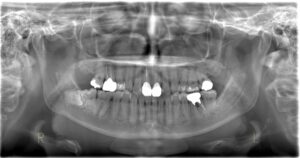

①虫歯の早期発見💡

歯と歯の間の虫歯や

詰め物の下に広がる虫歯は

目視では発見しづらいです。

ですがレントゲンを撮ることで

目視では見つけにくい部分も

撮影することができるので

早期発見することができます👀

②歯の根の先の状態が分かる💡

神経の状態や歯の根の先に

膿が溜まっているかどうかなど

歯茎の中の重要な情報が

レントゲンから得ることができます!

③歯周病の進行度が分分かる💡

歯を支えてる骨(歯槽骨)が

どのくらい減っているのかが

レントゲンで見ることができます。

④ 親知らずや歯並びを確認できる

埋まっている親知らずの位置や

向きを確認することができるので、

抜歯する際のリスクの判断にとても重要です!